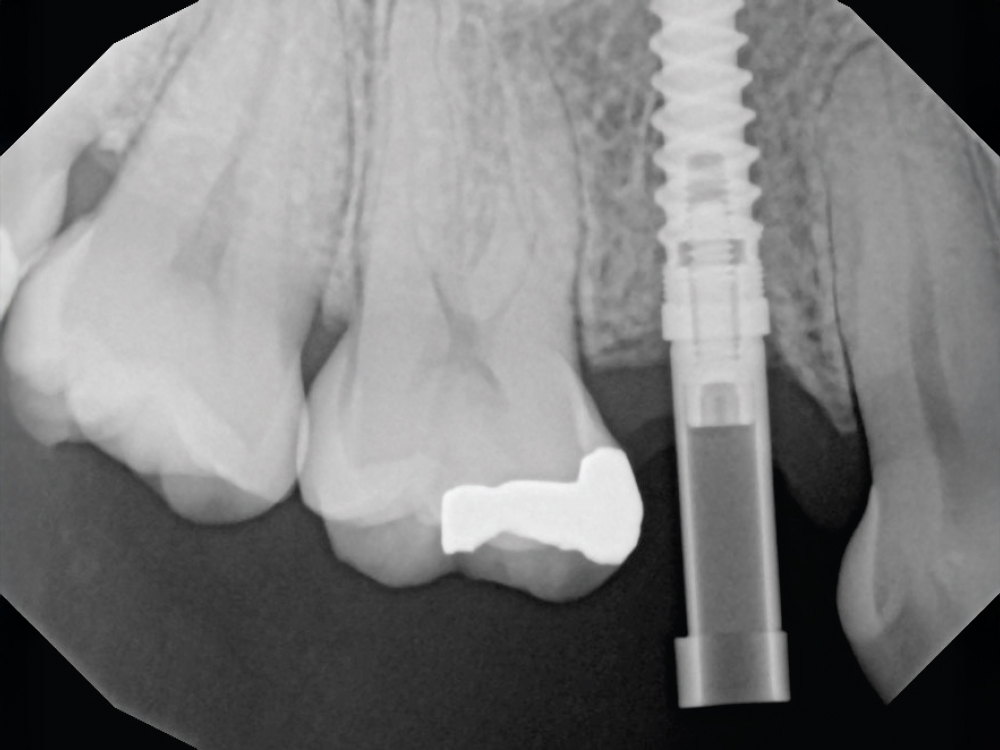

Verify Complete Scan Body Seating

Verify Complete Scan Body Seating. Confirm the scan body is fully seated to the implant before scanning — how it seats is precisely how the final restoration will seat. Use a radiograph if there is any question about complete seating, as an incompletely seated scan body will result in a restoration that does not fit, regardless of scan quality. Apply firm finger pressure or use a seating instrument, then verify there is no rocking or movement. Check for any tissue interference preventing complete seating and address it before scanning.

Thoroughly Scan the Scan Body Geometry

Thoroughly Scan the Scan Body Geometry. Complete, high-resolution capture of the scan body is non-negotiable. This is how laboratory software determines the precise three-dimensional position and angulation of the implant. The software matches the scanned scan body with its library file to establish the implant location in space. Scan from multiple angles to ensure all identifying features and surfaces are captured, as incomplete scan body data leads to misaligned restorations regardless of how perfect the rest of the scan appears. Verify that all reference markers, grooves, or geometric features are clearly visible in the acquired scan.